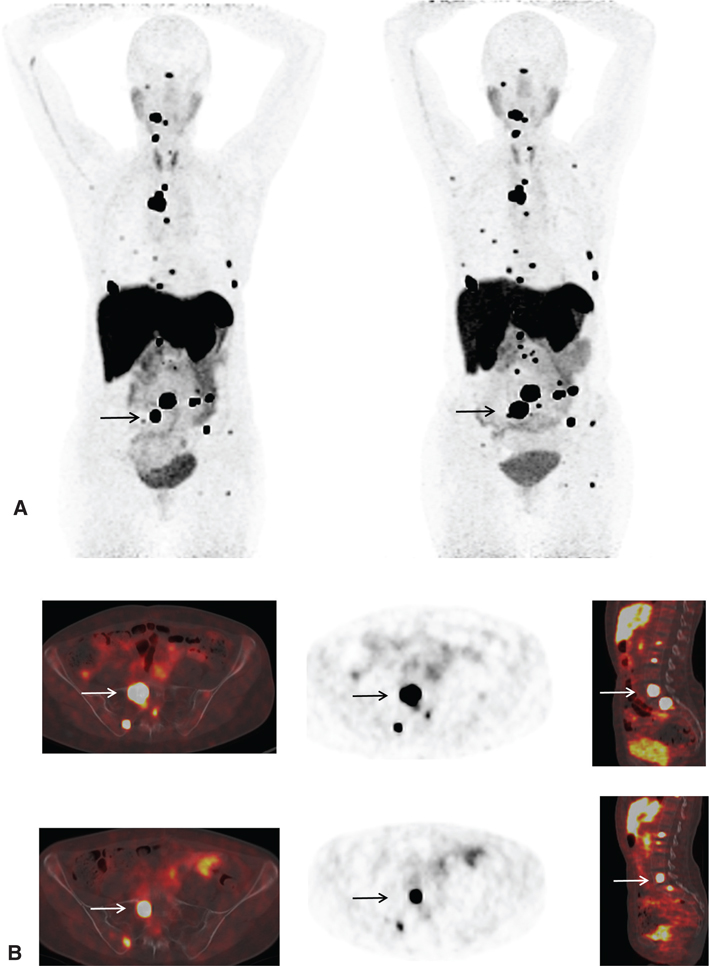

Fig 9

Figure 9 A 55-year-old woman with metastatic paraganglioma having an initial Ki67 proliferation index of 25% and strong SSTR2A immunostain but without SDHB mutation on germline testing. (A) Ga-68 DOTATATE PET/CT maximum intensity projection (MIP) images of the skull vertex to the proximal thigh on the left show widespread somatostatin receptor-positive metastatic disease, with progressive disease on the right image with enlarging pelvic osseous lesions (arrows). (B) Ga-68 DOTATATE PET/CT axial fused PET/CT, axial PET, and sagittal fused PET/CT images show enlarging vertebral lesion (arrows) on the current study (top images) as compared to the prior (bottom images).